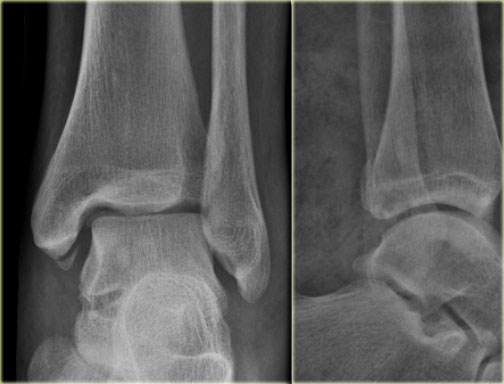

Weber-A stage I Weber-A stage I

Stage 1

The images show the usual Weber type A fractures.

These are all stage-1 fractures.

Stage-2 is extremely uncommon.

Notice the horizontal orientation of the fracture lines.

These are pull off type fractures as a result of avulsion.